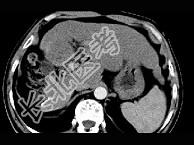

- 单项选择题女性,56岁, 腹胀、双下肢水肿、乏力、食欲不振,影像所见如下图, 最佳的诊断是  (    )

- A、酒精性肝硬化并肝血管瘤

- B、血吸虫肝硬化并肝癌

- C、肝炎后肝硬化并肝癌

- D、局限性脂肪肝

- E、原发性肝癌